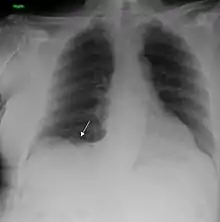

![]() | |

| A chest X-ray showing a tumor in the lung (marked by arrow) | |